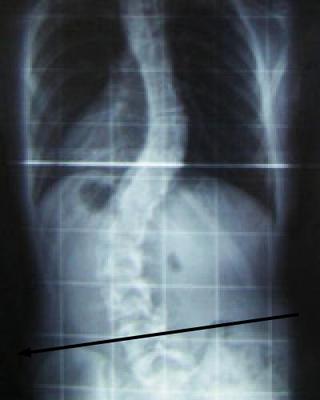

Do enquire whether you have a short leg; it greatly complicates any back.